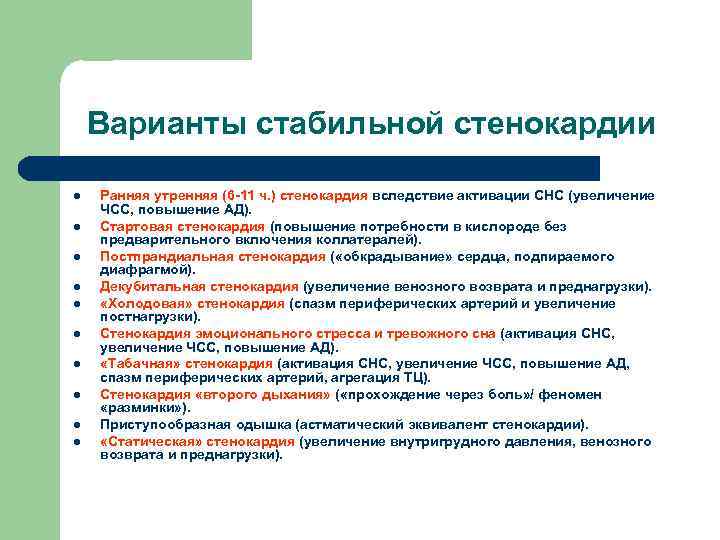

Варианты стабильной стенокардии l l l l l Ранняя утренняя (6 -11 ч. ) стенокардия вследствие активации СНС (увеличение ЧСС, повышение АД). Стартовая стенокардия (повышение потребности в кислороде без предварительного включения коллатералей). Постпрандиальная стенокардия ( «обкрадывание» сердца, подпираемого диафрагмой). Декубитальная стенокардия (увеличение венозного возврата и преднагрузки). «Холодовая» стенокардия (спазм периферических артерий и увеличение постнагрузки). Стенокардия эмоционального стресса и тревожного сна (активация СНС, увеличение ЧСС, повышение АД). «Табачная» стенокардия (активация СНС, увеличение ЧСС, повышение АД, спазм периферических артерий, агрегация ТЦ). Стенокардия «второго дыхания» ( «прохождение через боль» / феномен «разминки» ). Приступообразная одышка (астматический эквивалент стенокардии). «Статическая» стенокардия (увеличение внутригрудного давления, венозного возврата и преднагрузки).